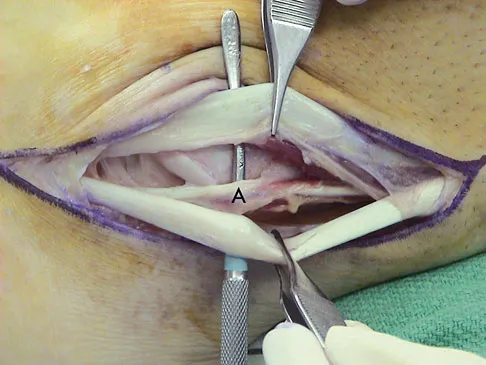

A 35-year-old man is seen for evaluation of his left ankle following multiple previous ankle sprains and frequent episodes of the ankle giving way. Examination reveals marked laxity about the lateral ankle with associated tenderness along the peroneal tendons. Physical therapy, anti-inflammatory drugs, and supportive bracing have failed to provide relief. An MRI scan shows peroneal tenosynovitis and a possible tear. He elects to undergo a peroneal tendon repair and lateral ligament reconstruction. Which of the following best describes the structure labeled "A" in Figure 45?

Explanation

The structure labeled "A" is a peroneus quartus, a supernumary muscle arising most commonly from the peroneus brevis. The presence of peroneus quartus is not uncommon, with an incidence of up to 21%, and is associated with lateral ankle pain and peroneal tendon symptoms, theoretically as a result of mass effect within the peroneal tendon sheath. Zammit J, Singh D: The peroneus quartus muscle: Anatomy and clinical relevance. J Bone Joint Surg Br 2003;85:1134-1137.